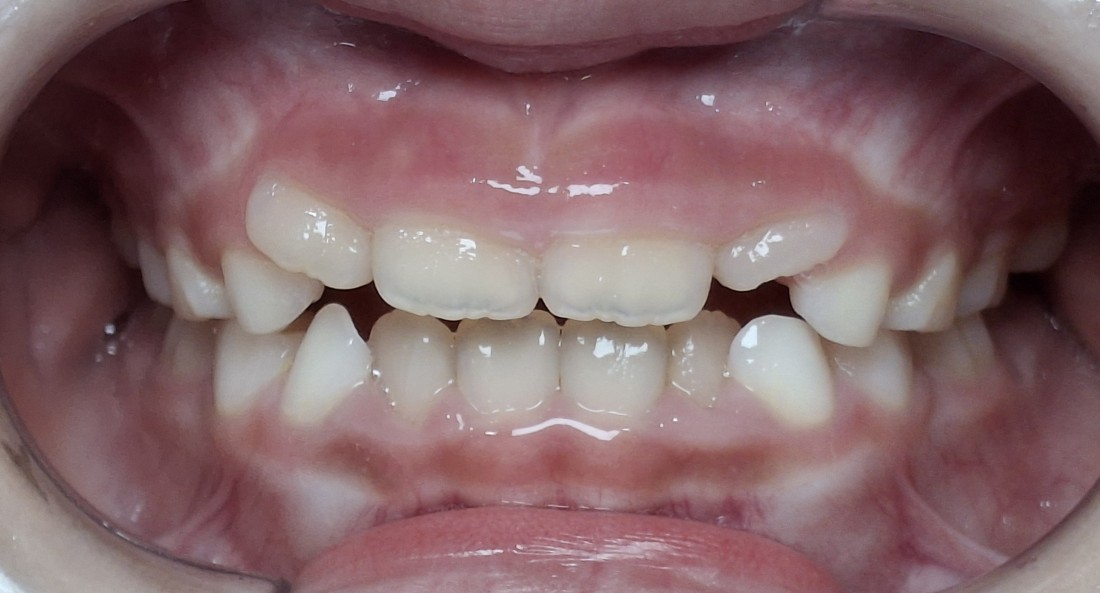

광주 어린이교정치과는

광주/전남에서 프리올소 사용량이

가장 많은 1위 치과입니다.

그만큼 오랜 기간

프리올소 사용 경험과 노하우를

축적해왔기 때문에

우리아이에게 맞는 최적의 교정계획을 세워

최상의 치료효과를 위해 노력합니다.